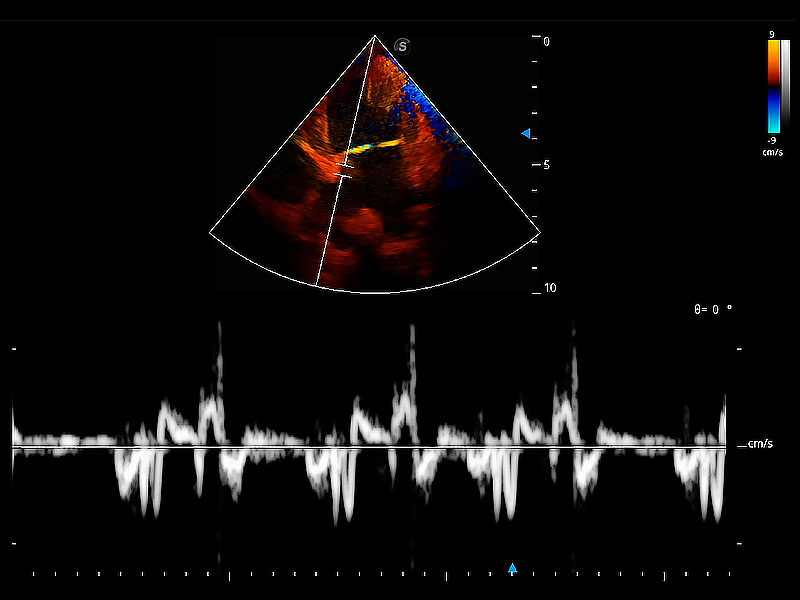

极大提升超低速微细血流的检出能力,同时更精准地滤除软组织和超声信号,为兽用医生提供以往无法通过常规血流获得的疾病诊断信息。

在传统二维血流成像的基础上,呈现血流的立体感,具有动感的生命力之美。即便是微小的血管也能轻松应对,提高了血流的视觉敏感性。

实时用颜色表示心肌组织运动,观察和定量组织的运动情況,对快速检测与评估心肌的灌注和活性、电传导及心肌收缩和舒张功能等均能提供重要的诊断信息。